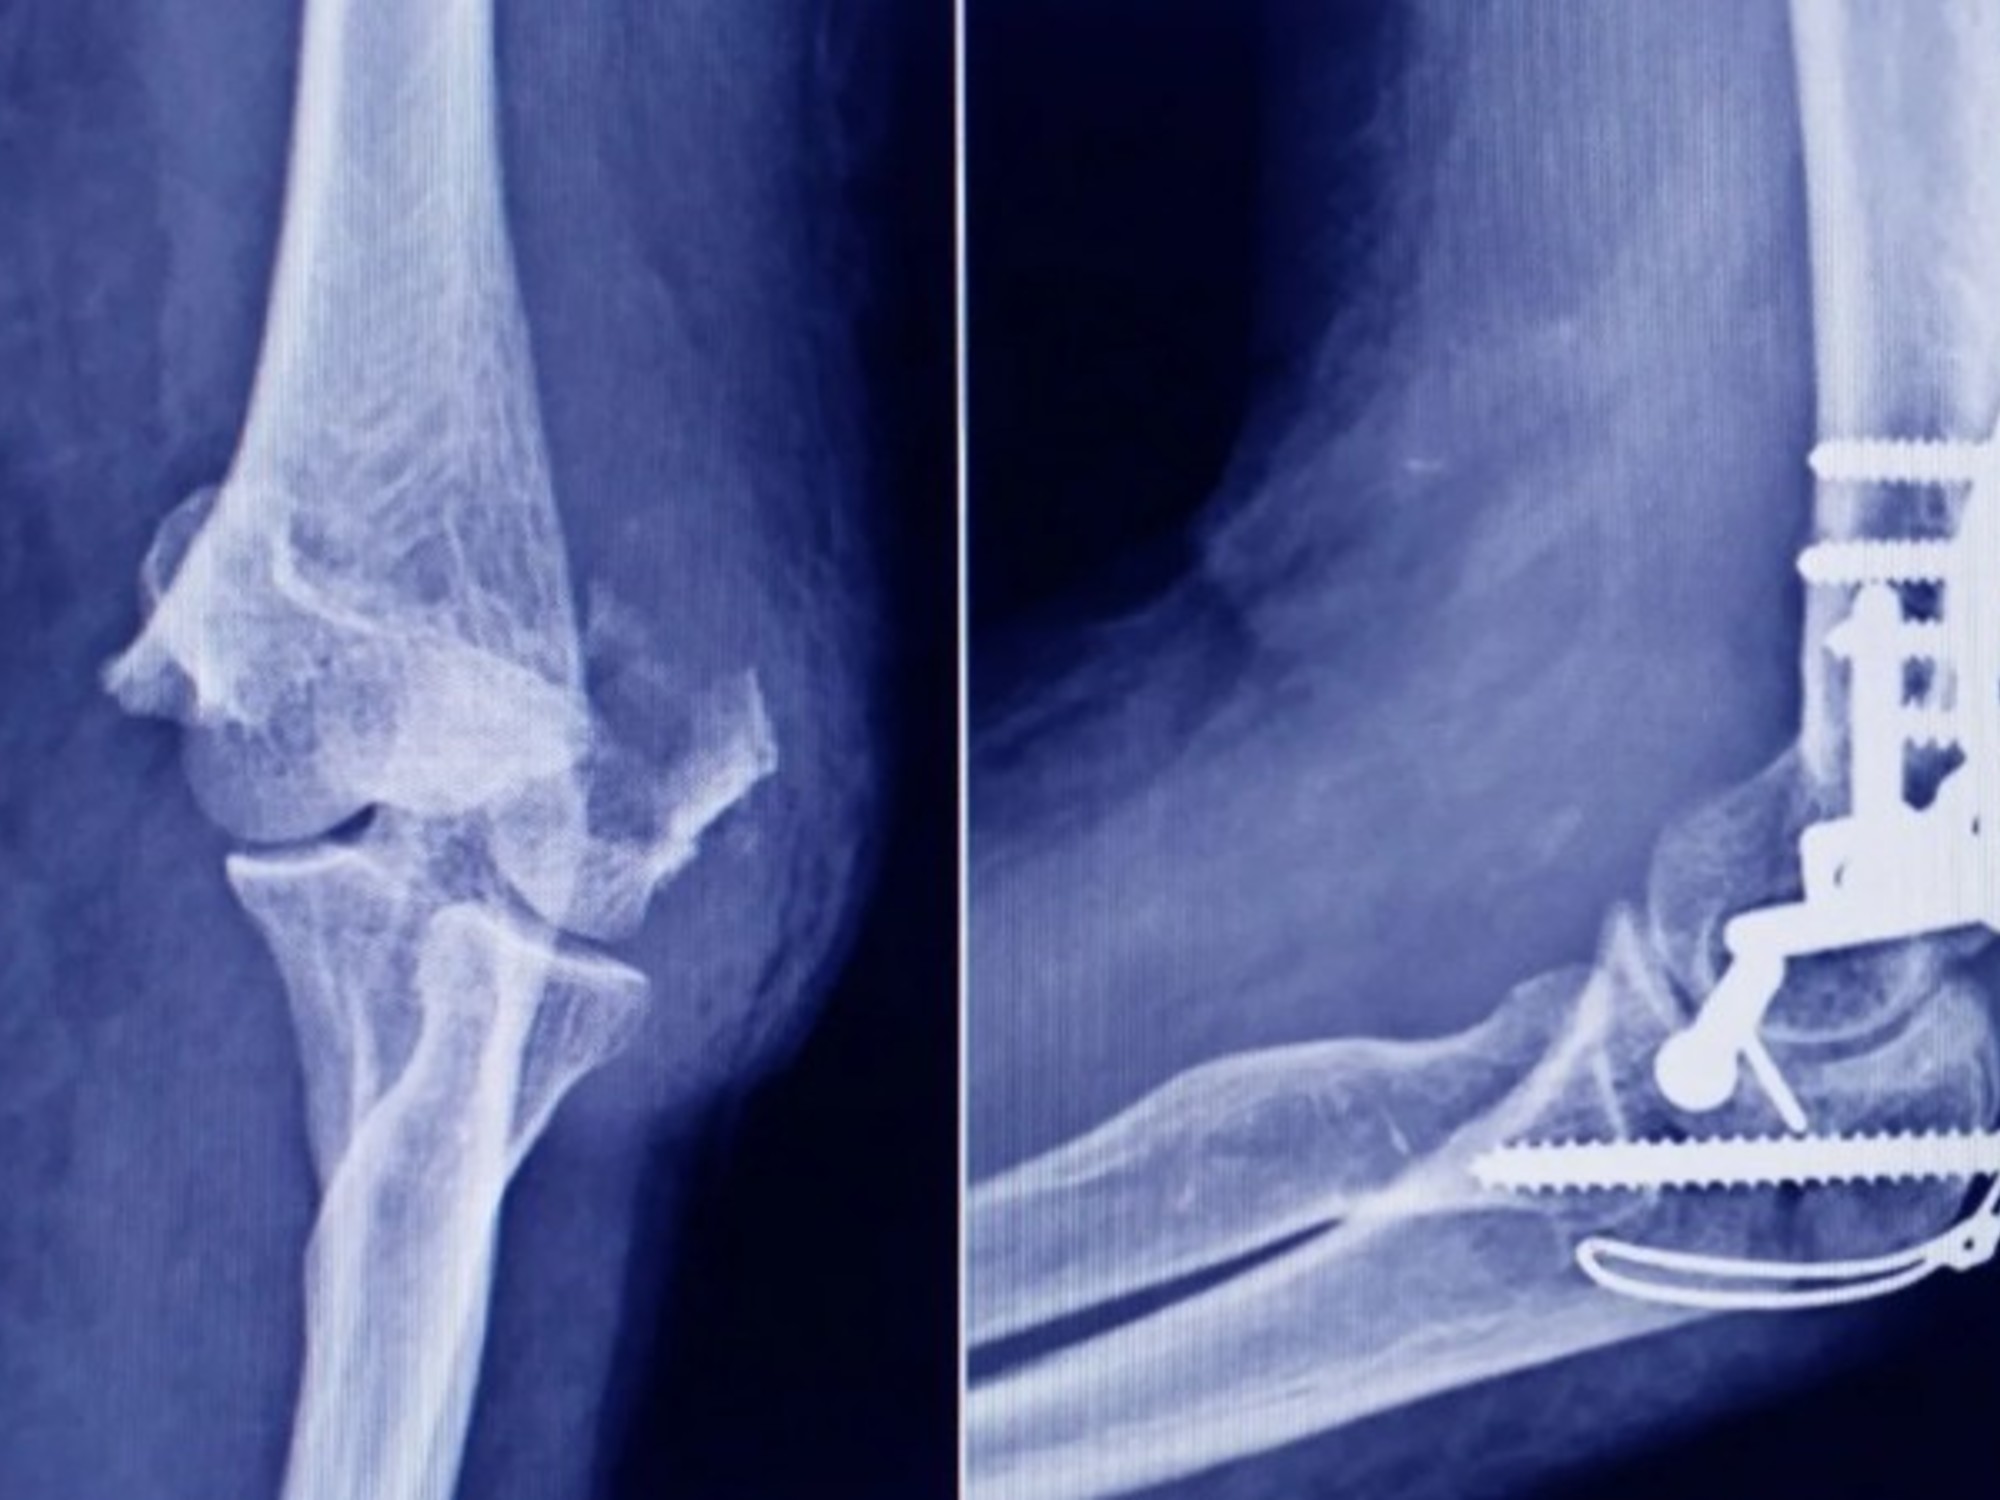

La Administración Nacional de Medicamentos, Alimentos y Tecnología Médica (ANMAT) ha emitido una alerta tras descubrir un tornillo utilizado en cirugías traumatológicas que se comercializa de forma ilegal. Este tornillo, procedente de la firma Stryker Corporation, fue encontrado en una ortopedia en San Miguel de Tucumán durante una inspección rutinaria.

El tornillo en cuestión, que mide 10 mm x 28 mm, fue confirmado como falsificado tras un análisis de características clave. La representante técnica de Stryker señaló que el producto carecía de la fecha de vencimiento que caracteriza a los artículos originales, una de las principales diferencias detectadas.

Al comparar ambos productos, se observó que el tornillo original es de color gris opaco, mientras que el falsificado es incoloro y no ha sido esterilizado adecuadamente. Mientras que Stryker utiliza radiación gamma para la esterilización, el tornillo falso parece haber sido tratado con vapor o formaldehído, lo que compromete su seguridad.

El uso de este tornillo no solo pone en riesgo la salud de los pacientes, sino que también plantea interrogantes sobre su composición y origen. Por este motivo, ANMAT ha instado a la población a que, si poseen este producto, eviten su uso y se comuniquen con el organismo para informar sobre la situación.